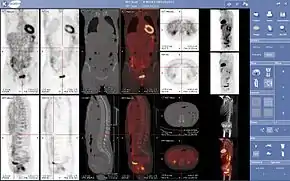

PET scanners can incorporate a CT scanner and are known as PET-CT scanners. PET scan images can be reconstructed using a CT scan performed using one scanner during the same session.

Combination of PET with CT or MRI

PET scans are increasingly read alongside CT or magnetic resonance imaging (MRI) scans, with the combination (called "co-registration") giving both anatomic and metabolic information (i.e., what the structure is, and what it is doing biochemically). Because PET imaging is most useful in combination with anatomical imaging, such as CT, modern PET scanners are now available with integrated high-end multi-detector-row CT scanners (so-called "PET-CT"). Because the two scans can be performed in immediate sequence during the same session, with the patient not changing position between the two types of scans, the two sets of images are more precisely registered, so that areas of abnormality on the PET imaging can be more perfectly correlated with anatomy on the CT images. This is very useful in showing detailed views of moving organs or structures with higher anatomical variation, which is more common outside the brain.